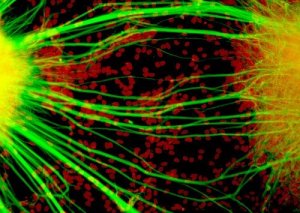

Da circa 15 anni i ricercatori hanno notato che trapiantando cellule staminali neurali negli animali, queste ultime sortivano in loro un effetto benefico, portando a una remissione molto significativa della malattia, a tal punto che animali già paralizzati riuscivano a riprendere a camminare. Le direzioni della ricerca scientifica intorno a questo fenomeno negli anni sono state due: primo, capire se lo stesso risultato fosse riscontrabile anche nell’uomo e secondo quali fossero i meccanismi coinvolti in questo fenomeno, cioè capire perché succede.

Un’ulteriore buona notizia giunge dai laboratori del San Raffaele dove è stato fatto un altro passo avanti rispetto ai meccanismi che possono spiegare l’effetto terapeutico e che devono ancora essere dettagliatamente individuati: dietro il successo di questi trattamenti a basso dosaggio di cellule staminali neurali ci sarebbe una proteina – TGF-β2 – che viene rilasciata proprio dalle cellule staminali infuse, e che interferisce con l’attività infiammatoria del cervello, riducendola. La modulazione che le cellule staminali riescono a fare attraverso TGF-β2 sulle cellule mieloidi che mantengono lo stato infiammatorio dei linfociti T, i diretti responsabili del danno cerebrale, è fondamentale.